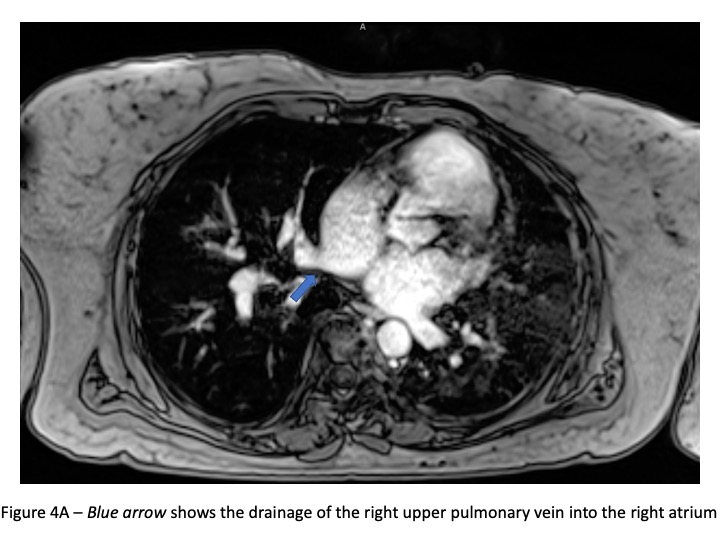

The differential diagnosis of a dilated right heart is broad. The possibilities include Ebstein anomaly, primary pulmonary hypertension, chronic lung disease, arrhythmogenic right ventricular cardiomyopathy, and other congenital heart lesions such as an atrial septal defect or a coronary artery fistula. Though congenital heart disease is less likely in an elderly patient, this should still be considered. The ECG (Figure 3) is non-specific but shows increased right sided voltages and 1st degree heart block. A transthoracic echo showed right heart dilation (Figure 1), but pulmonary vein abnormalities are challenging to ascertain in the setting of sub-optimal echo windows in an elderly patient. A subsequent cardiac MRI confirmed the presence of right heart dilation, and anomalous drainage of the right upper and right lower pulmonary veins into the right atrium (PAPVR) ( Figure 4A-D).

Figure 4A